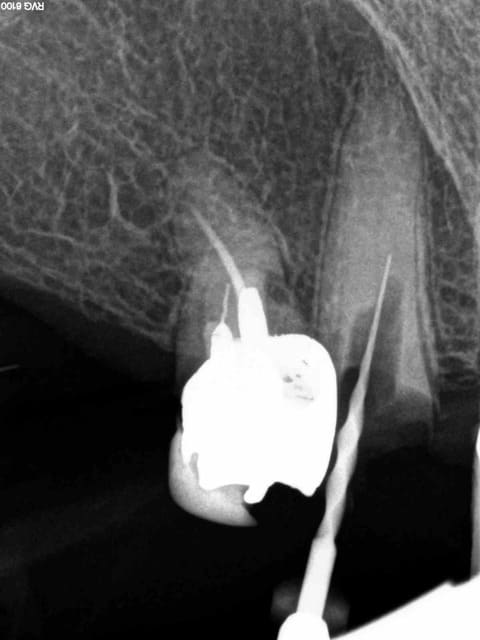

Arrivé un moment ou tu te dis que tu vas l'extraire, mais tu ne le fais pas parceque ca fait 3/4 d'heures que tu cherches ce putain de canal. Et enfin la lumière fut ( c'est le cas de le dire). -)))))

1 nfmvd7 - Eugenol

2 dvdqtt - Eugenol

3 f3ohf3 - Eugenol

4 zmohou - Eugenol

5 j0htr8 - Eugenol

6 e86kdq - Eugenol

7 fbttie - Eugenol